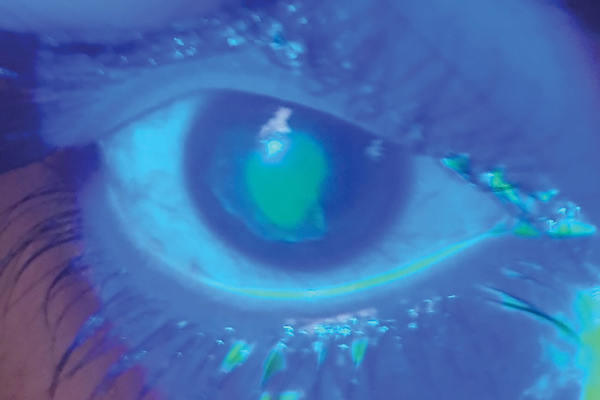

Laser corneal refractive procedures – a review